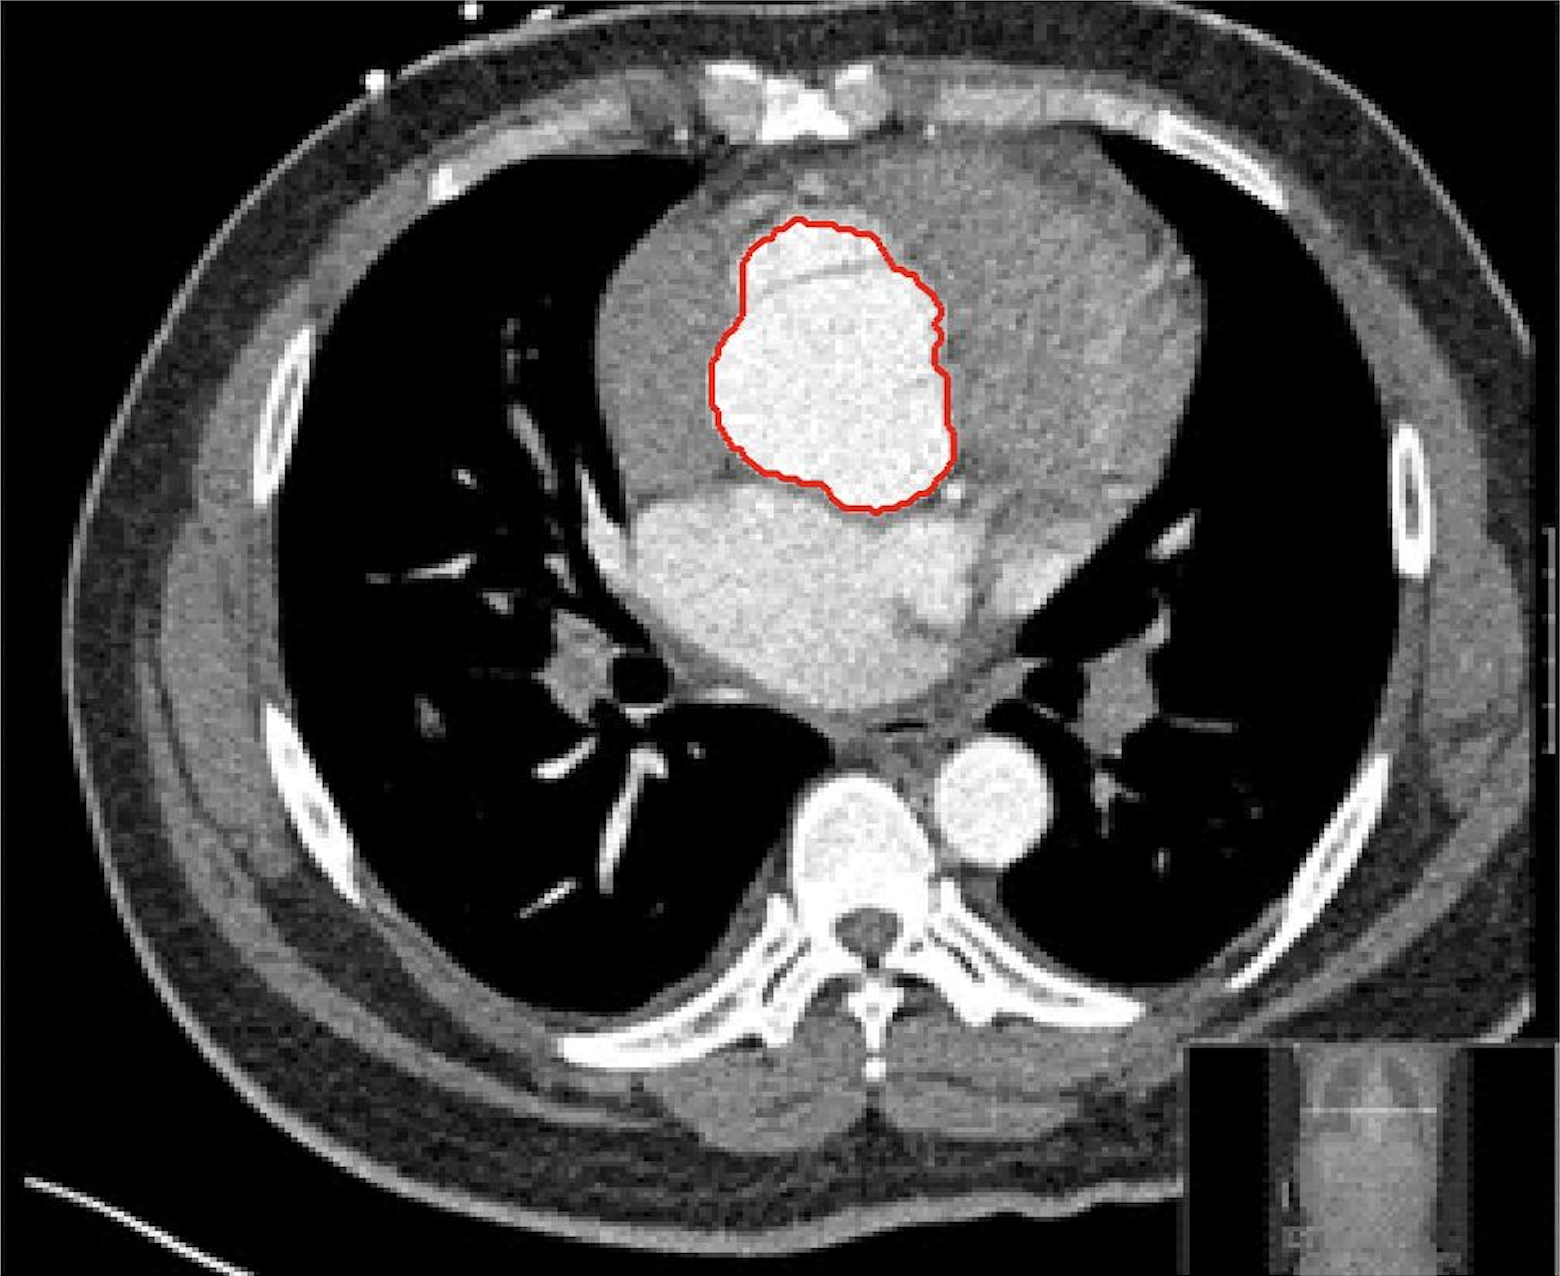

Four sets of test results are shown below. In Test 1 we compare models M1 – M6 to the proposed model M7 for two images which are hard to segment. The first is a CT scan from which we would like to segment the lower portion of the heart, the second is an MRI scan of a knee and we would like to segment the top of the Tibia. See Figure 9 for the test images and the marker sets used in the experiments. In Test 2 we will review the sensitivity of the proposed model to the main parameters. In Test 3 we will give several results achieved by the model using marker and anti-marker sets. In Test 4 we show the initialisation independence and marker independence of the Geodesic Model on real images.

In this test we give the segmentation results for models M1 – M7 for the two challenging test images shown in Figure 9. The marker and anti-marker sets used in the experiments are also shown in this figure. After extensive parameter tuning, the best final segmentation results for each of the models are shown in Figures 10 and 11. For M1 – M4 we obtain incorrect segmentations in both cases. In particular, the results of M2 and M4 are interesting as the former gives poor results for both images, and the latter gives a reasonable result for Test Image 1 and a poor result for Test Image 2. In the case of M2, the regularisation term includes the edge detector and the distance penalty term (see (4)). It is precisely this which permits the poor result in Figures 10(b) and 11(b) as the edge detector is zero along the contour and the fitting terms are satisfied there (both intensity and area constraints) – the distance term is not large enough to counteract the effect of these. In the case of M4, the distance term and edge detector are separated from the regulariser and are used to weight the Chan-Vese fitting terms (see (9)). The poor segmentation in Figure 11(b) is due to the Chan-Vese terms encouraging segmentation of bright objects (in this case), weighting enforces these terms at all edges in the image and near . In experiments, we find that M4 performs well when the object to segment is of approximately the highest or lowest intensity in the image, however when this is not the case, results tend to be poor. We see that, in both cases, models M5 and M6 give much improved results to M2 and M4 (obtained by incorporating the geodesic distance penalty into each). The proposed Geodesic Model M7 gives an accurate segmentation in both cases. It remains to compare M5, M6 and M7. We see that M5 is a non-convex model (and cannot be made convex [39]), therefore results are initialisation dependent. It also requires one more parameter than M6 and M7, and an accurate set to give a reasonable area constraint in (4). These limitations lead us to conclude M6 and M7 are better choices than M5. In the case of M6, it has the same number of parameters as M7 and gives good results. M6 can be viewed as the model M7 with weighted intensity fitting terms (compare (18) and (30)). Experimentally, we find that the same quality of segmentation result can be achieved with both models generally, however M6 is more parameter sensitive than M7. This can be seen in the parameter map in Figure 12 with M7 giving an accurate result for a wider range of parameters than M6. To show the improvement of M7 over previous models, we also give an image in Figure 13 which can be accurately segmented with M7 but the correct result is never achieved with M6 (or M3). Therefore we find that M7 outperforms all other models tested M1 – M6.

Test 3 – Further Results from the Geodesic Model M7. In this test we give some medical segmentation results obtained using the Geodesic Model M7. The results are shown in Figure 14. In the final two columns we use anti-markers to demonstrate how to overcome blurred edges and low contrast edges in an image. These are challenging and it is pleasing to see the correctly segmented results.

(i) (ii) (iii) (iv) (v)